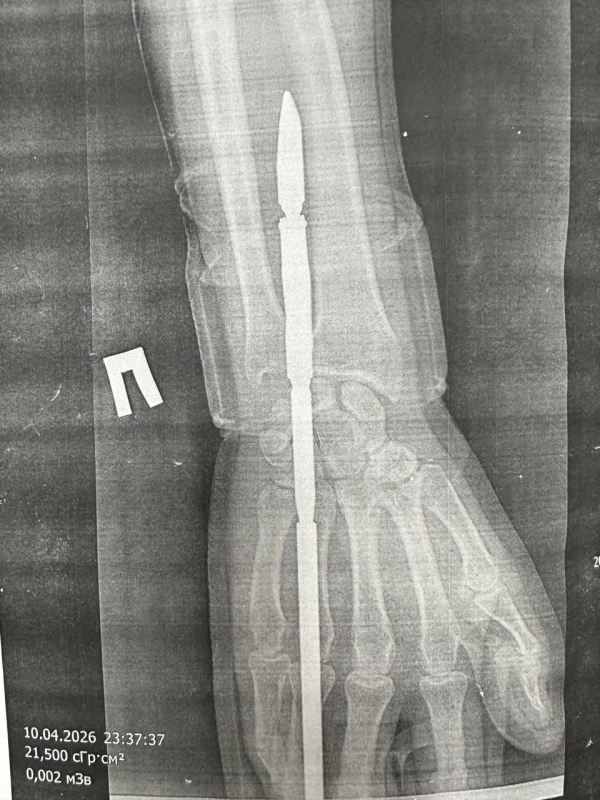

В ГАУЗ «ГБ» г. Орска рассказали, что гарпун с двумя зубцами прошёл между костями, не задев их.

Специалисты извлекли инородное тело, обработали рану и оказали пациенту всю необходимую помощь.

Сейчас пострадавший находится в хирургическом стационаре.